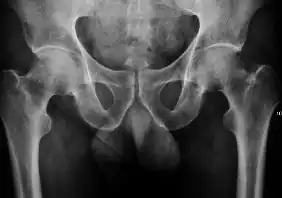

Projectional radiography ("X-ray") is the first imaging technique of choice in hip pain, not only in older people with suspected osteoarthritis but also in young people without any such suspicion. In this case plain radiography allows categorization as normal hip or dysplastic hip, or with impingement signs, pincer, cam, or a combination of both.[1]

X-Ray

Projectional radiography ("X-ray") is currently useful not only in older people in whom osteoarthritis of the hip is suspected but also in younger people without osteoarthritis, who are being evaluated for femoroacetabular impingement (FAI) or hip dysplasia.[1]

Plain radiography allows us to categorize the hip as normal or dysplastic or with impingement signs (pincer, cam, or a combination of both). Besides these, pathologic processes like osteoarthritis, inflammatory diseases, infection, or tumors can also be identified (Figure 1).[1]

Figure 1.

-

Radiography in normal hip -

X-ray in pincer impingement type of hip dysplasia -

X-ray of cam -

Hip in osteoarthritis -

Septic arthritis